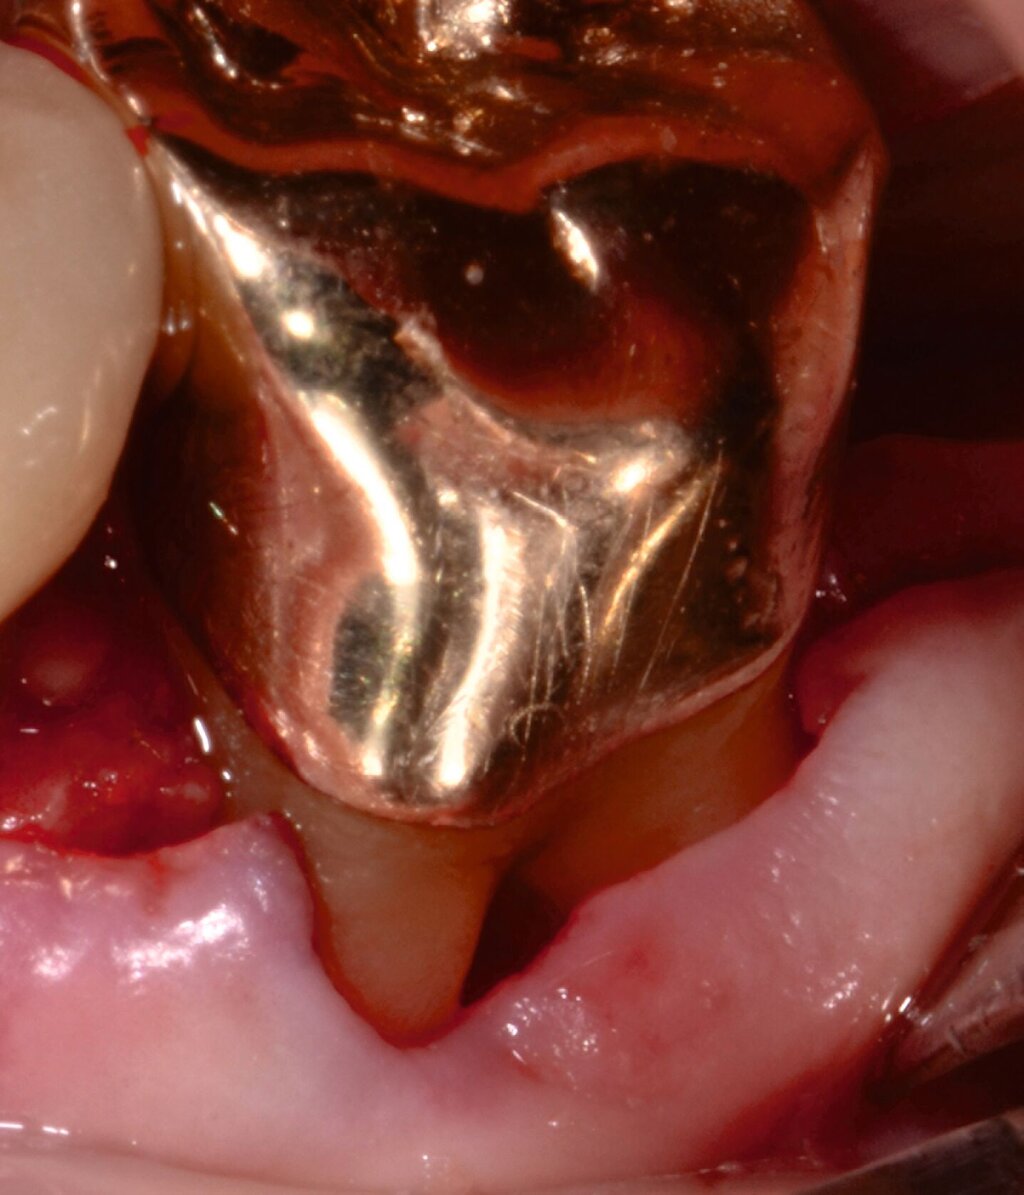

Fall 3 – komplex